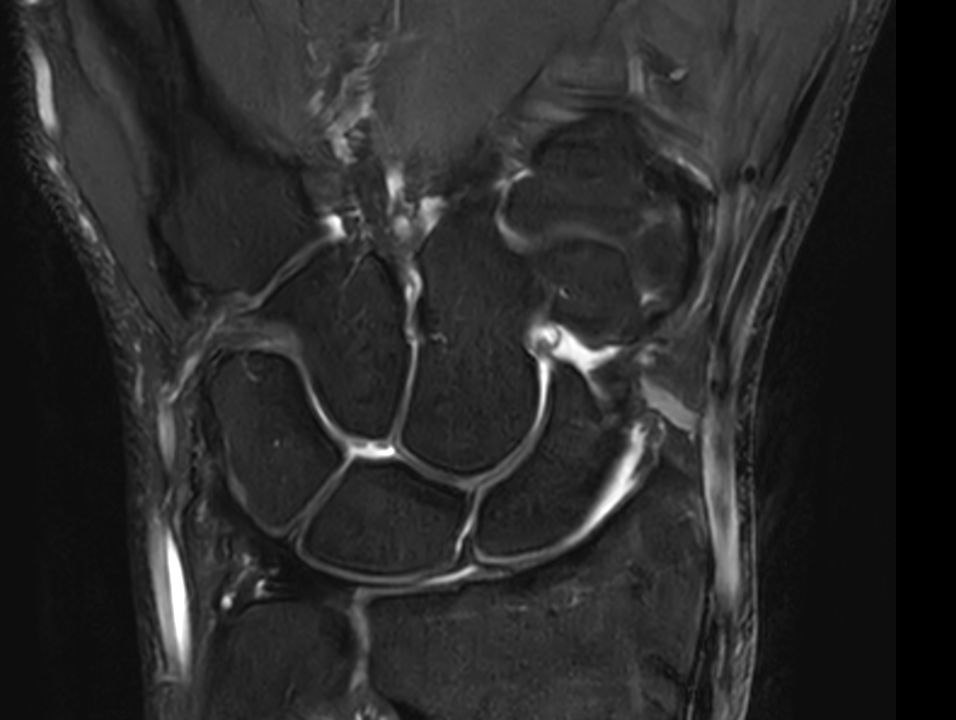

Coronal T2w TSE FatSat

Coronal T2w TSE FatSatSmartSpeed

Coronal T2w TSE FatSatSmartSpeed Resolution